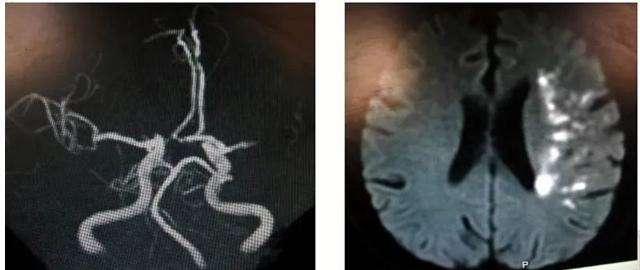

图9 头部MRI示左侧额叶、双侧顶叶多发急性脑梗死病灶,MRA正常;经食道超声提示卵圆孔未闭(图源 作者提供)

二、心源性

急性多发梗死灶,双侧前循环/前后循环;有心源性卒中证据;无相应颅内外大动脉粥样硬化证据;无其他病因(血管炎、凝血异常、肿瘤栓塞等);如排除主动脉弓粥样硬化,为肯定的心源性,如不能排除,为可能的心源性。